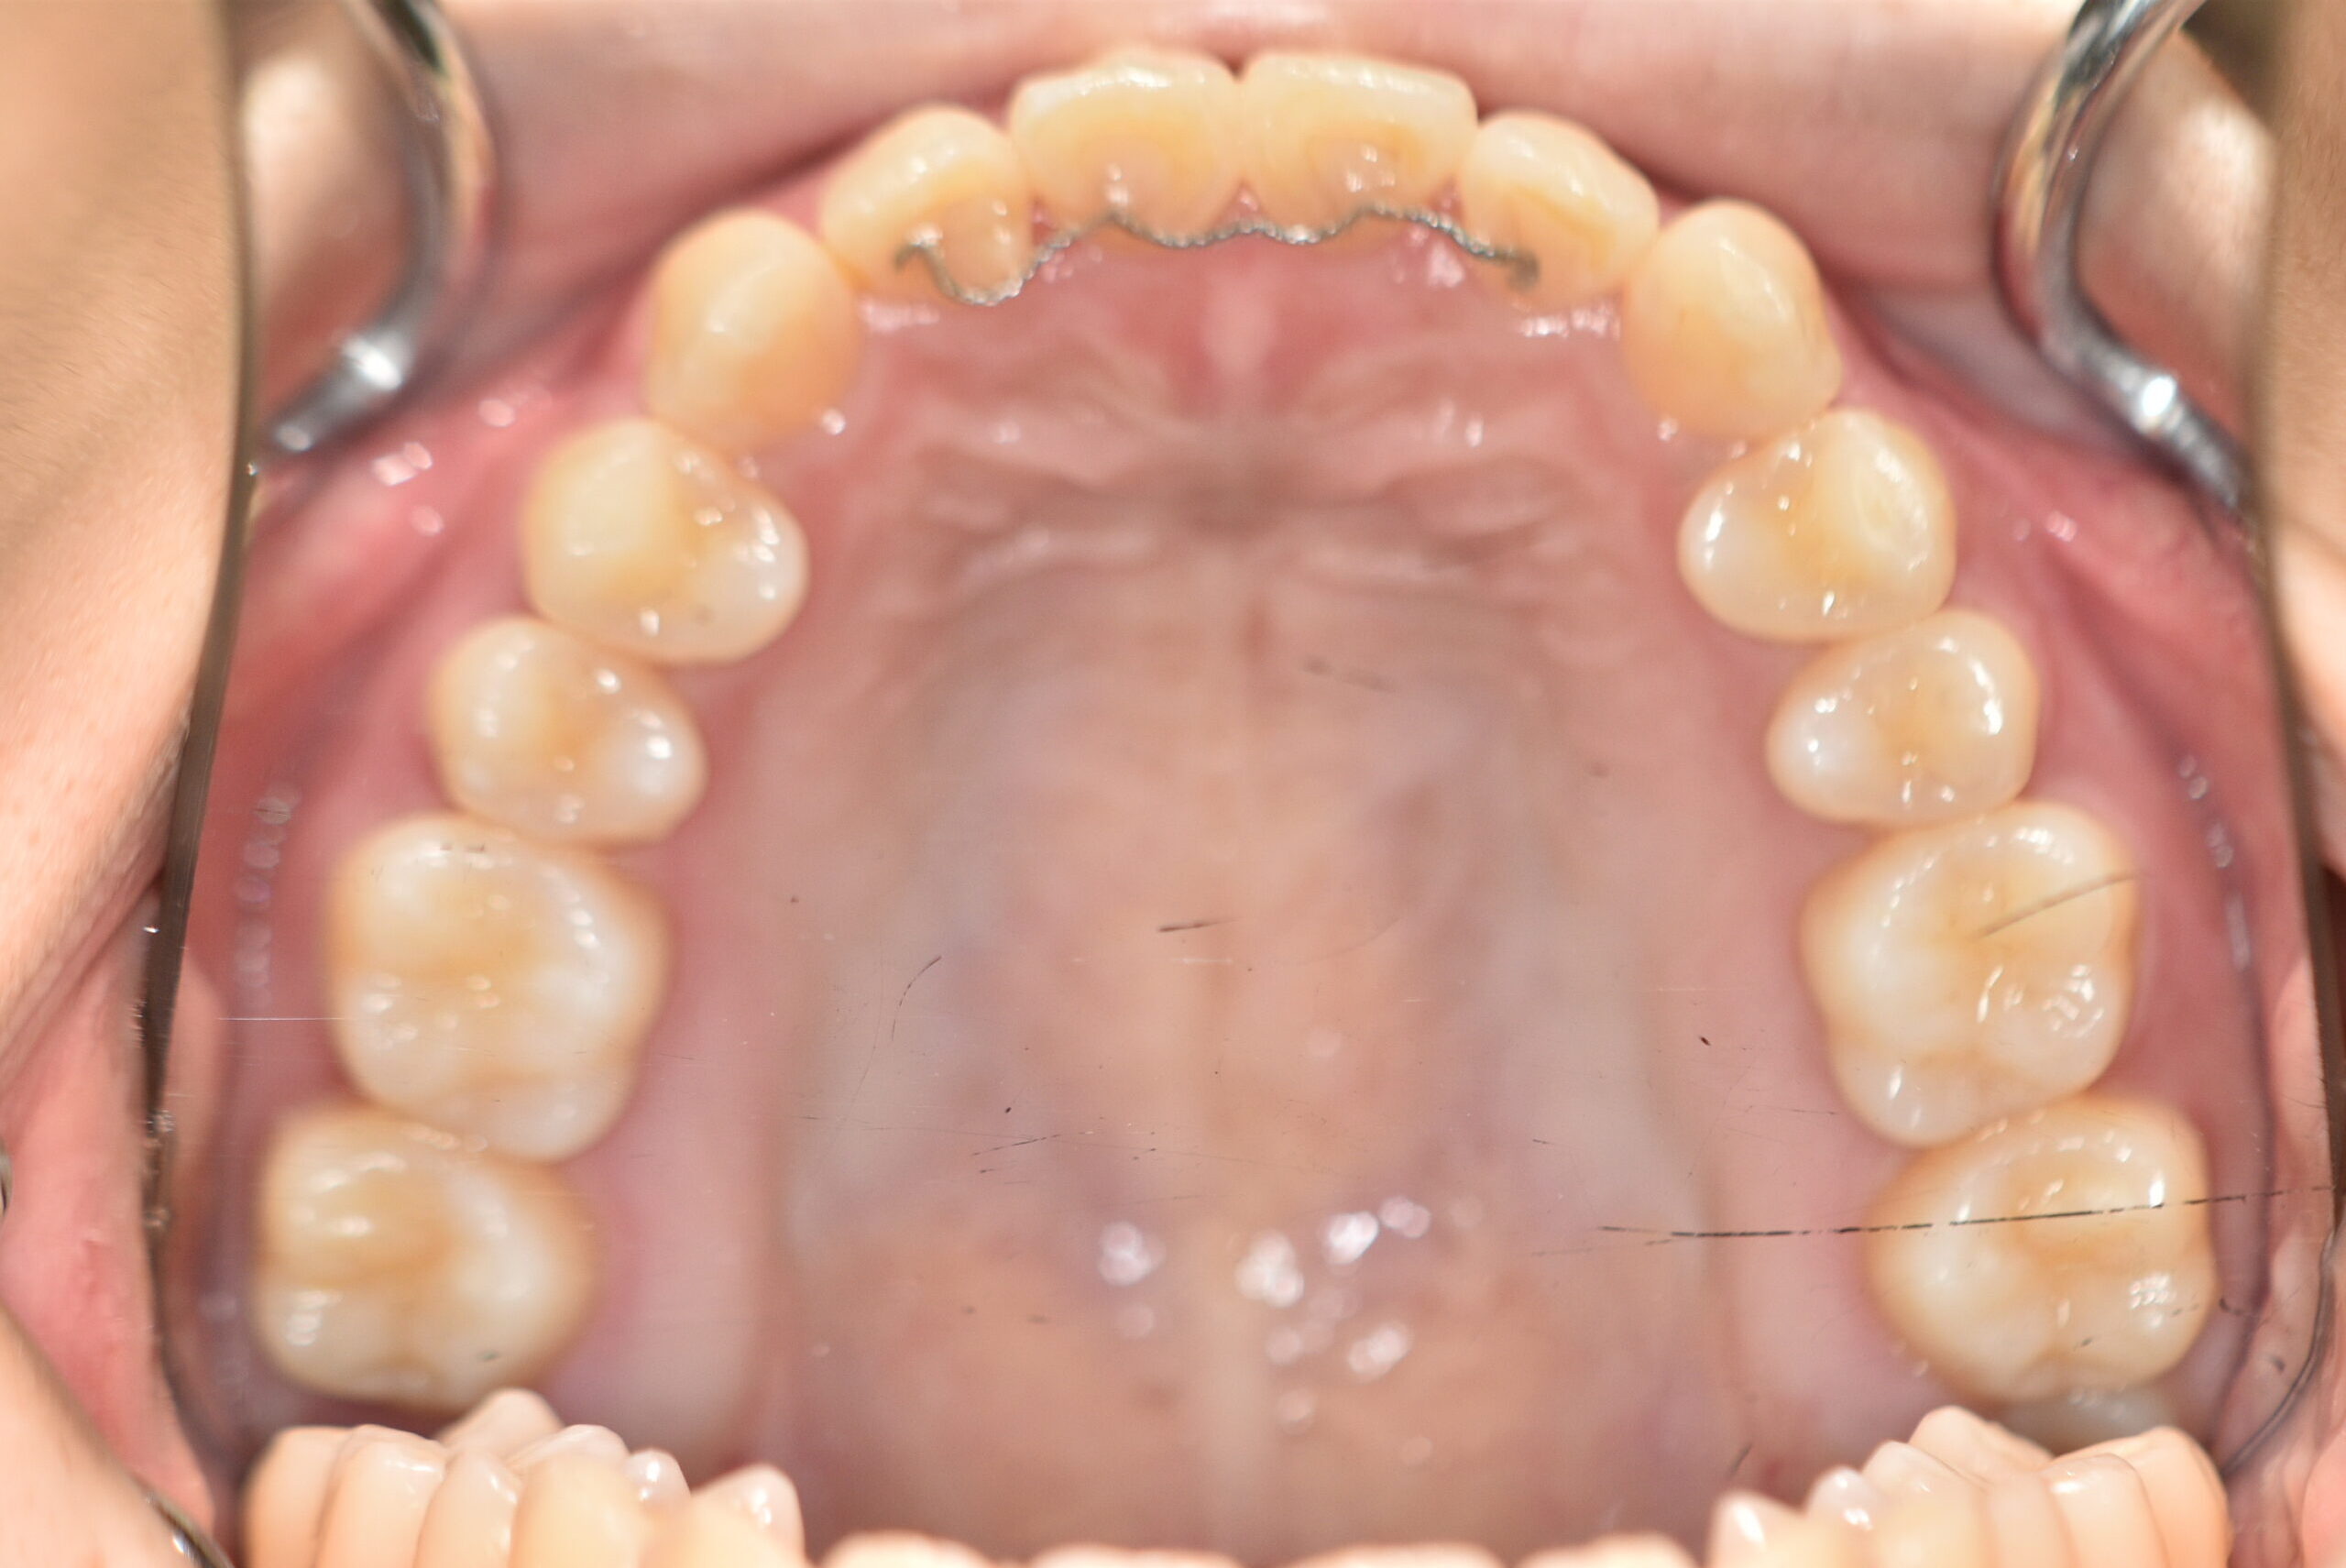

初診時

治療内容の詳細 初診時17歳の女性で、かみ合わせが悪く少しガタガタしていることをを気にされ来院されました。

検査の結果、上下顎叢生を伴うアングル1級不正咬合と診断しました。

治療としては、非抜歯の上、マウスピース型矯正装置(インビザライン)で歯の配列を行いました。